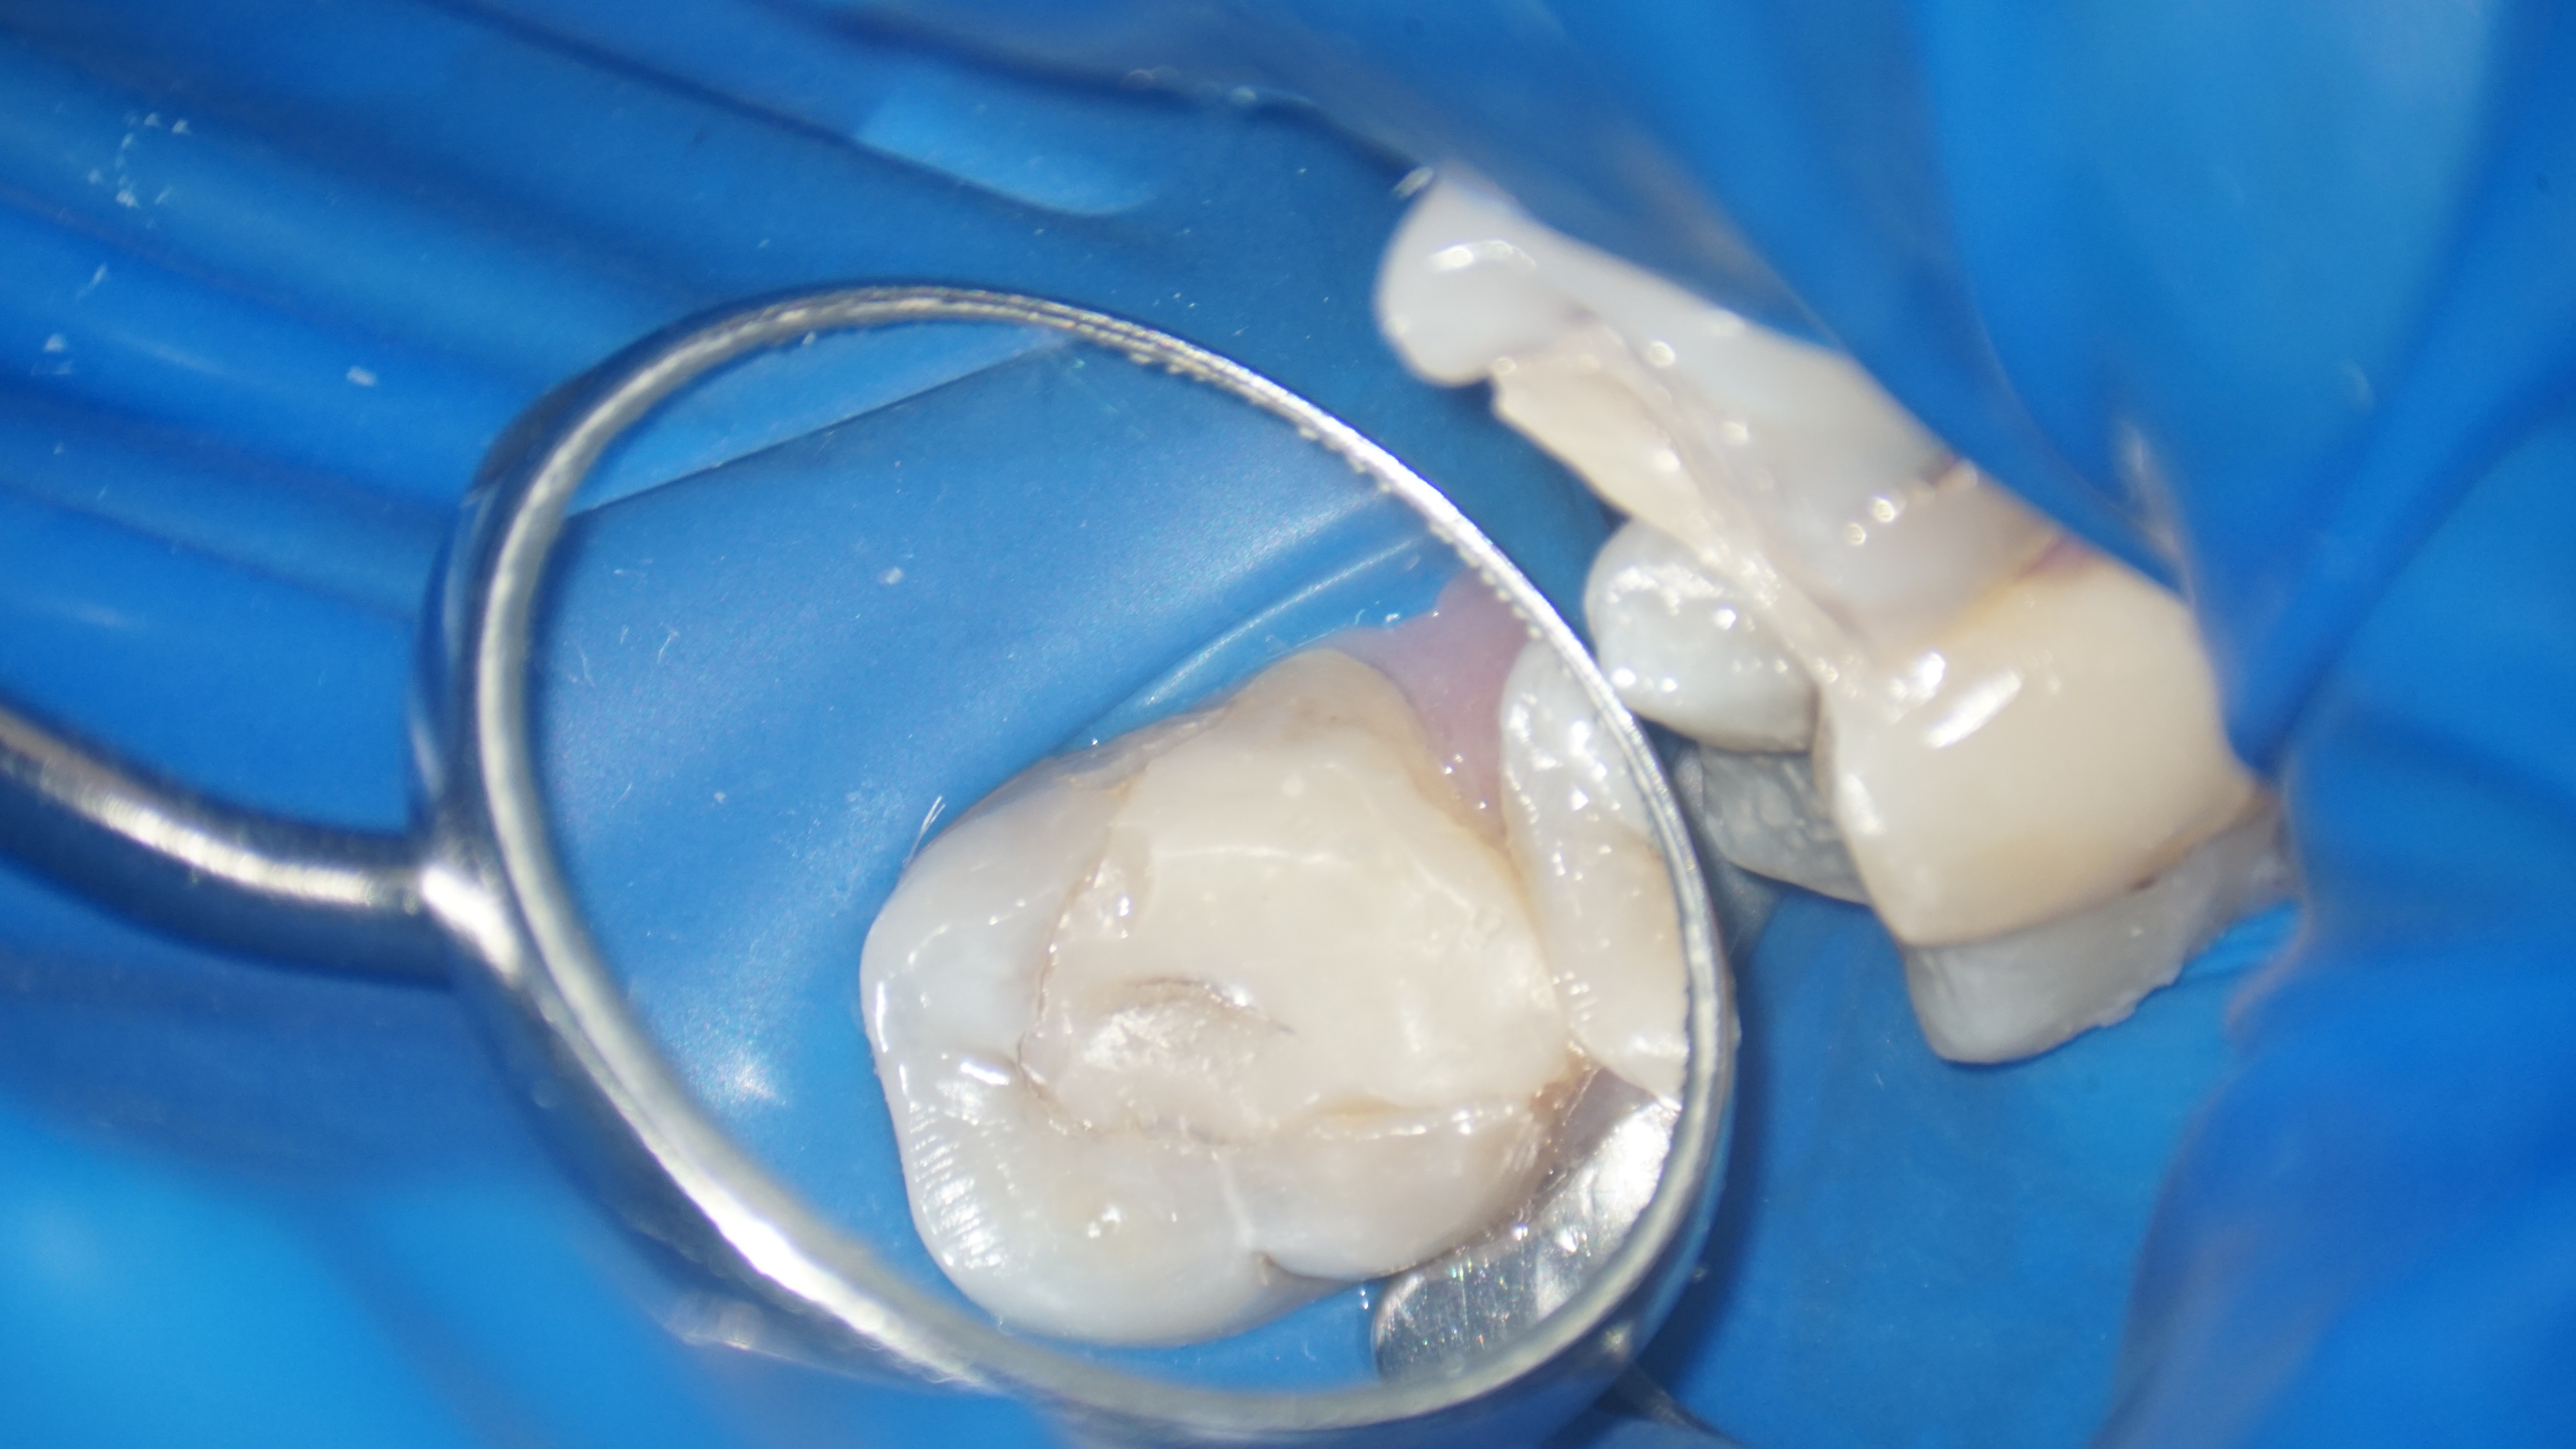

Astfel, s-a decis refacerea tratamentului iniţial, fapt ce a implicat instrumentarea canalelor radiculare și curățarea lor adecvată, realizând bypass-ul (ocolirea) fragmentului din rădăcina mezială şi înlăturarea celui din rădăcina distală. După finalizarea procedurilor, pacientul a raportat dispariția simptomatologiei și ameliorarea disconfortului la masticatie.

În concluzie, cazul a fost abordat cu succes prin efectuarea unui tratament endodontic și prin managementul al fragmentelor de ace ce împiedicau instrumentarea adecvată a spaţiului endodontic. Aceste proceduri au avut ca rezultat vindecarea patologiei și ameliorarea simptomatologiei, restabilind sănătatea și funcționalitatea dintelui.